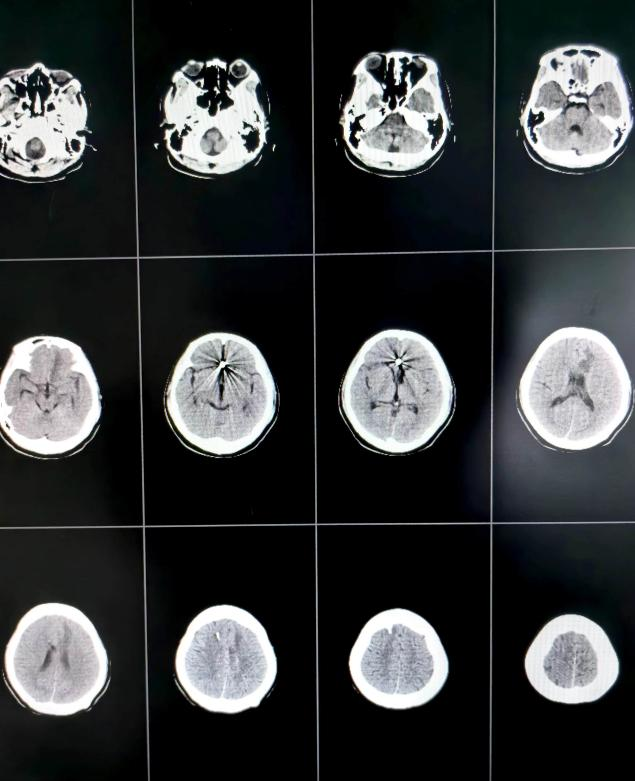

36岁的患者马女士(化名)因“突发意识不清3小时”从临近县医院转入我院,外院CT示蛛网膜下腔出血。来院时,马女士意识已陷入昏迷,频繁恶心呕吐,频发癫痫肢体抽搐。马女士进入急诊医学科后,脑科医院院长纪文军主任医师立即指示开通绿色通道,急诊复查头颅CT示左侧额叶脑出血、脑室积血、蛛网膜下腔出血;脑干受压、密度减低。相比于第一次CT出血明显增多,考虑为颅内动脉瘤二次破裂所致。

术前头颅CT提示颅内血肿、脑室积血、蛛网膜下腔出血

术后第13天头颅CT示颅内出血引流完全,脑室无扩大

由于患者意识昏迷状态,自主呼吸弱,给予气管插管呼吸机辅助呼吸,护理团队给予患者特级护理,进一步引流颅内积血及血性脑脊液,术后第3天再给患者行腰大池引流术。在神经外科二病区医护团队的精心治疗护理下,患者术后第6天顺利脱呼吸机,术后第13天完全清醒,肢体肌力逐渐恢复正常。现患者意识清楚,四肢无明显偏瘫等神经功能障碍,现已康复出院。